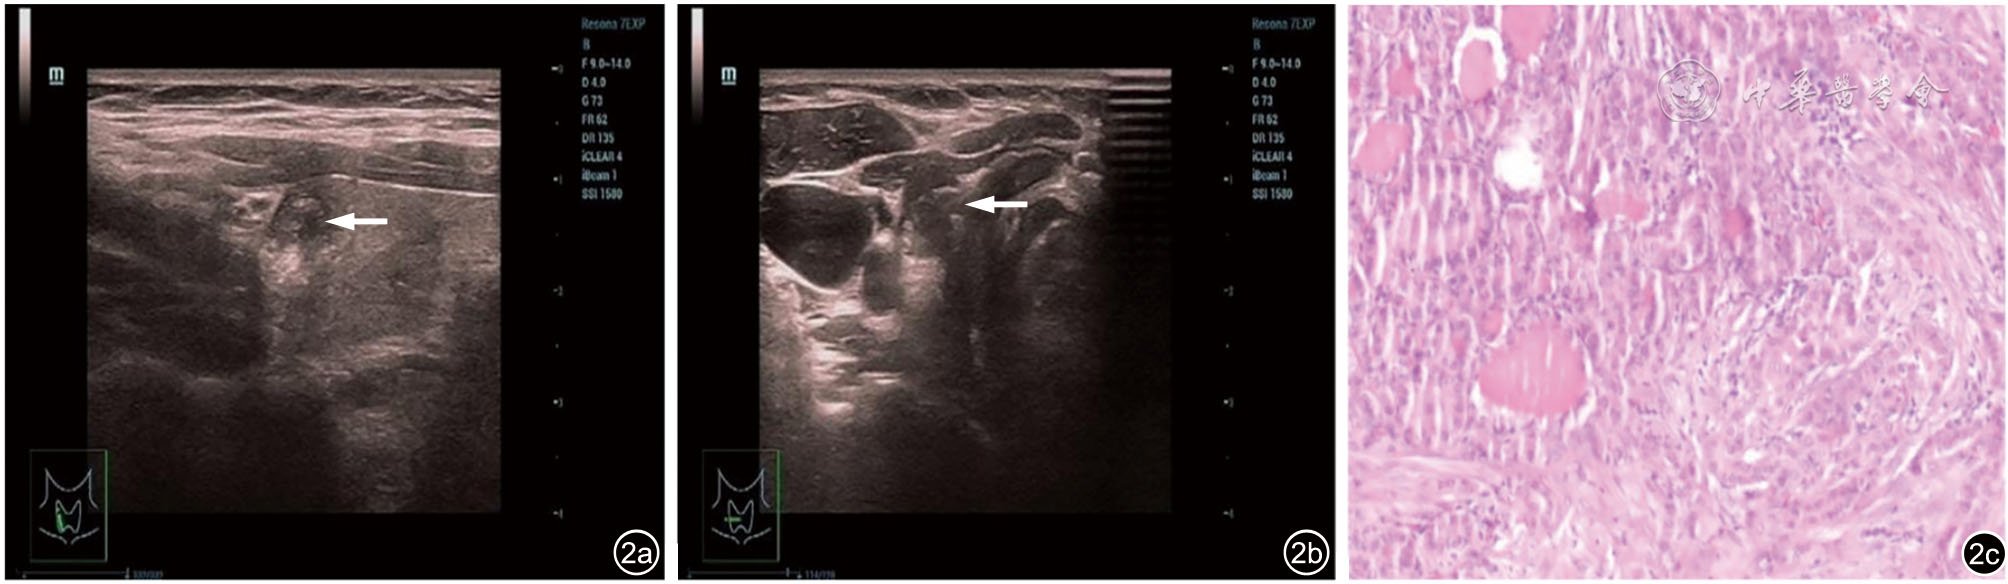

Diagnostic performance of ACR TI-RADS versus C-TIRADS for thyroid micronodules

To compare the diagnostic value of the American College of Radiology thyroid imaging reporting and data system (ACR TI-RADS) and Chinese thyroid imaging reporting and data system (C-TIRADS) in thyroid micronodules.

A total of 1213 patients with 1599 thyroid micronodules confirmed by surgical pathology were enrolled. According to the ACR TI-RADS and C-TIRADS, thyroid micronodules were evaluated and scored. Using surgical pathology as the golden standard, a ROC curve was constructed to determine the optimal cut-off value. Nodules with scores above the cutoff were classified as malignant, while those below as benign. The diagnostic efficacy of ACR TI-RADS and C-TIRADS systems for thyroid microcarcinomas was then analyzed and compared by DeLong test.